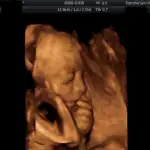

3D/4D ultrazvuk

Tyto fotografie jsou pořízené přístrojem Voluson 730